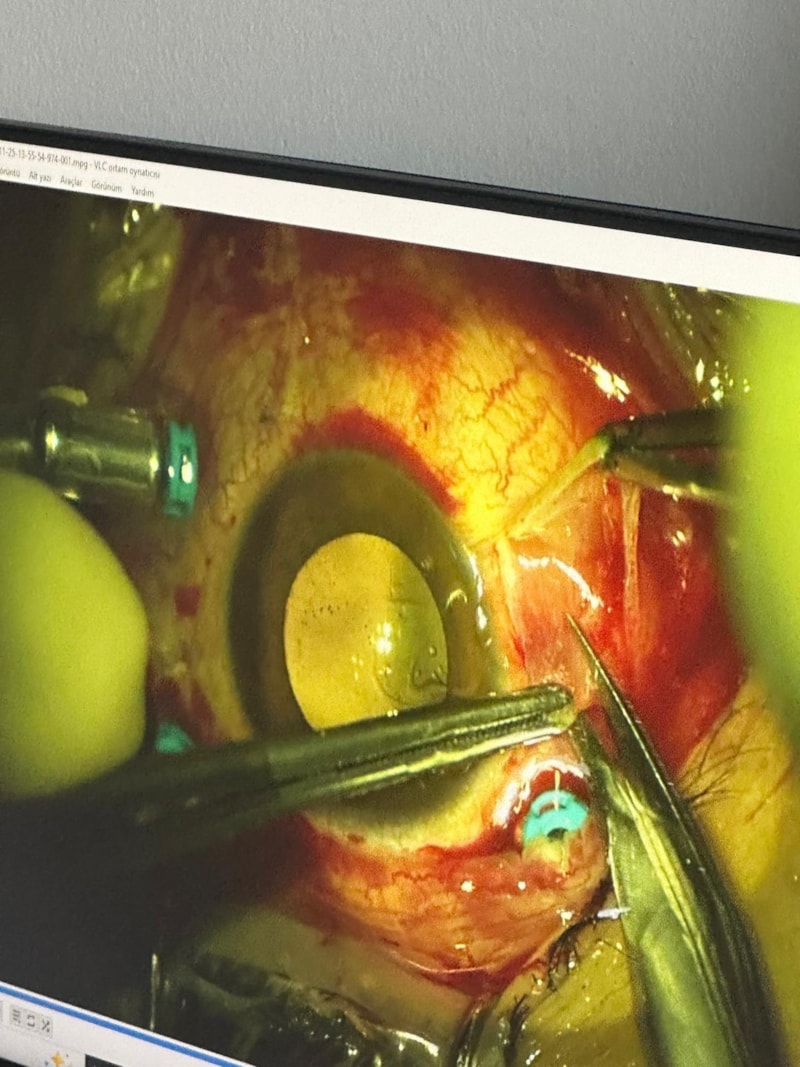

Sağlık ekipleri; damadın saçmalar nedeniyle gözünden, başından ve kulağından yaralandığını tespit etti.

İlk müdahalenin ardından Nevşehir Devlet Hastanesi'ne kaldırılan Mert G., daha sonra ileri tedavi için Kayseri Erciyes Üniversitesi Tıp Fakültesi Hastanesi'ne sevk edildi.

"Müvekkilim ile eşi bir süredir ayrı yaşıyor. Müvekkilim, eşinin talebi üzerine evde unuttuğu özel eşyayı kayınpederinin evine götürüyor. Aracında eşini beklerken kayınpederi elindeki tüfekle araca ateş ediyor. Saçmalar hem araca hem müvekkilime isabet ediyor. Şu ana kadar dört operasyon geçirmesine rağmen görmesinde bir iyileşme sağlanamadı. Göz nakli gerekebilir. Araçta yaklaşık 20 saçma izi var. Müvekkilimin gözünde, kulağında ve başında saçmalar bulunuyor."